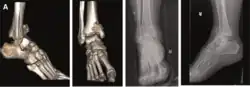

| Supination-Adduction |

|

![]() |